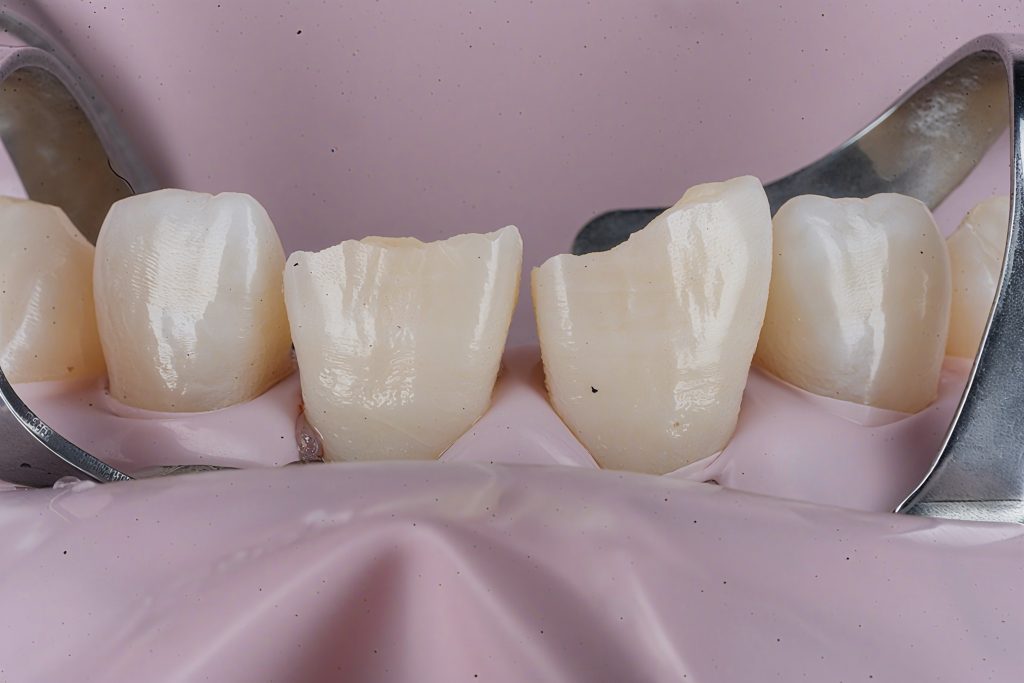

2. Rubber Dam Isolation

A pink dam clamp setup was used to stabilise the working field, protect the gingiva, and maintain clean bonding conditions.

5. Layering Strategy (Bio-Emulation)

Palatal Shell

- A clear matrix was positioned to mimic the natural incisal curvature.

- A translucent enamel shade was placed to form the palatal wall.

Mamelon Build-Up

- A body shade (Clearfil Majesty Body) was sculpted in mamelon patterns.

- Depth effect enhanced with grey/ochre stains.

Halo & Incisal Translucency

- A white tint was used to create a natural incisal halo band.

- Layered translucent enamel shade to cover stains subtly.

Facial Layering

- Thin enamel layers were added to control value, avoiding excessive opacity.